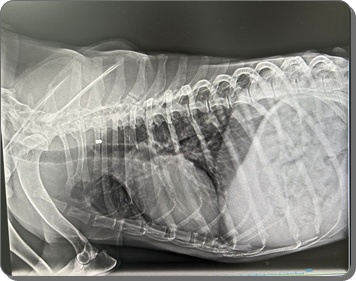

Der Abdomen erscheint ebenfalls mit Flüssigkeit gefüllt, sodass der Verdacht

auf eine kardiale Problematik geäußert wurde.

In der Röntgenuntersuchung der Gliedmaßen wurden Veränderungen festgestellt,

die auf eine beginnende Osteoporose hinweisen, sodass die Knochenstruktur

als nicht gesund bewertet wird und eine erhöhte Fragilität

(leichteres Brechen) anzunehmen ist.